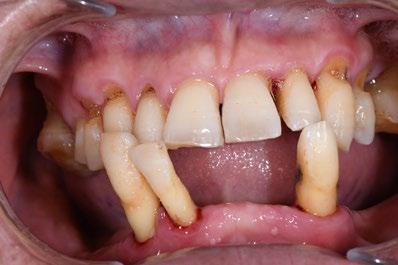

❷ 严重牙周病

当牙周病已经导致牙齿松动严重,无法通过治疗来稳固时,可能需要拔除患牙。